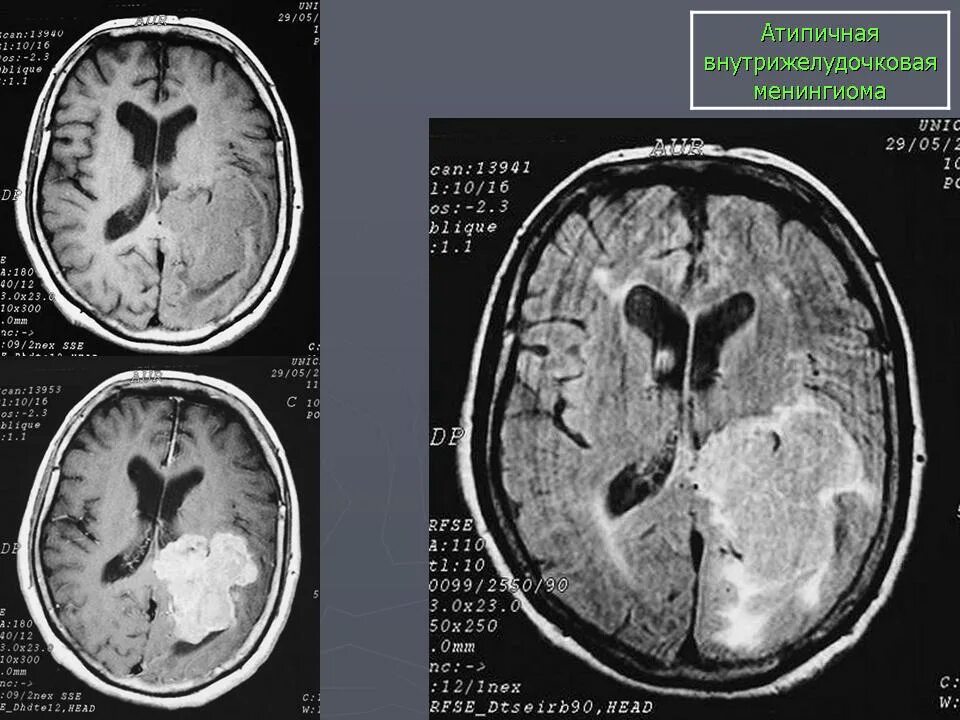

Менингиомы головного мозга мкб